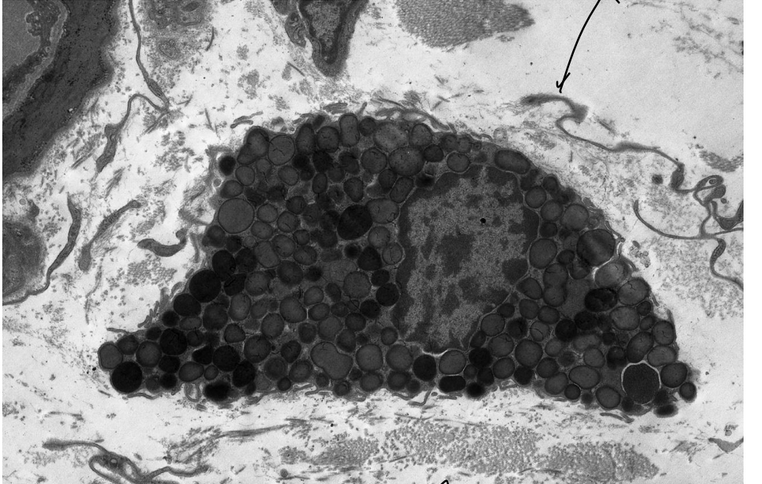

mastocyte